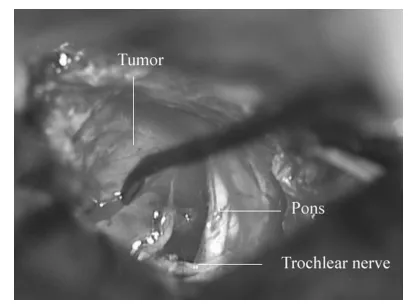

采用经岩前入路手术。实施右颞开颅术,从中颅窝底抬起硬脑膜,保留岩浅大神经。磨除后内侧三角骨质,切开颞部及后颅窝硬脑膜,结扎岩上窦后切开窦壁及天幕。见肿瘤位于天幕缘下方,滑车神经位于肿瘤后下极,神经末端呈扇形与肿瘤融合,确认肿瘤起源于滑车神经。

右经岩前入路术后术野所见。肿瘤起源于滑车神经,神经末端呈扇形与肿瘤融合。

肿瘤内含黄色囊液,与三叉神经无关联。未能窥及位于桥前蛛网膜后方的动眼神经与外展神经。因肿瘤与脑干边界清晰且未粘连重要血管,顺利分离周边结构后切断滑车神经实现肿瘤全切。